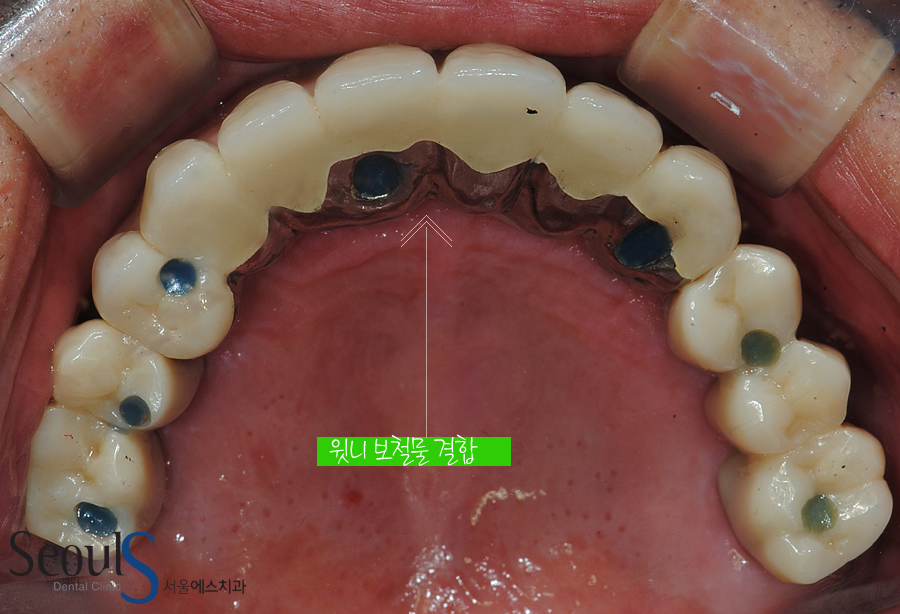

윗니도 보철물을 결합했습니다

상악동 거상술 잇몸뼈이식, 코밑 뼈이식을 통해 임플란트 7개를 식립했고

환자분께 어울리는 최상의 보철물 제작 후 결합했습니다

윗니 역시 이쁘고 튼튼하게 치료가 마무리된 모습입니다

잇몸 부분을 보시면 자연스러운 치아를 만들기 위해

잇몸 부분도 잇몸 색 포세린으로 제작했습니다